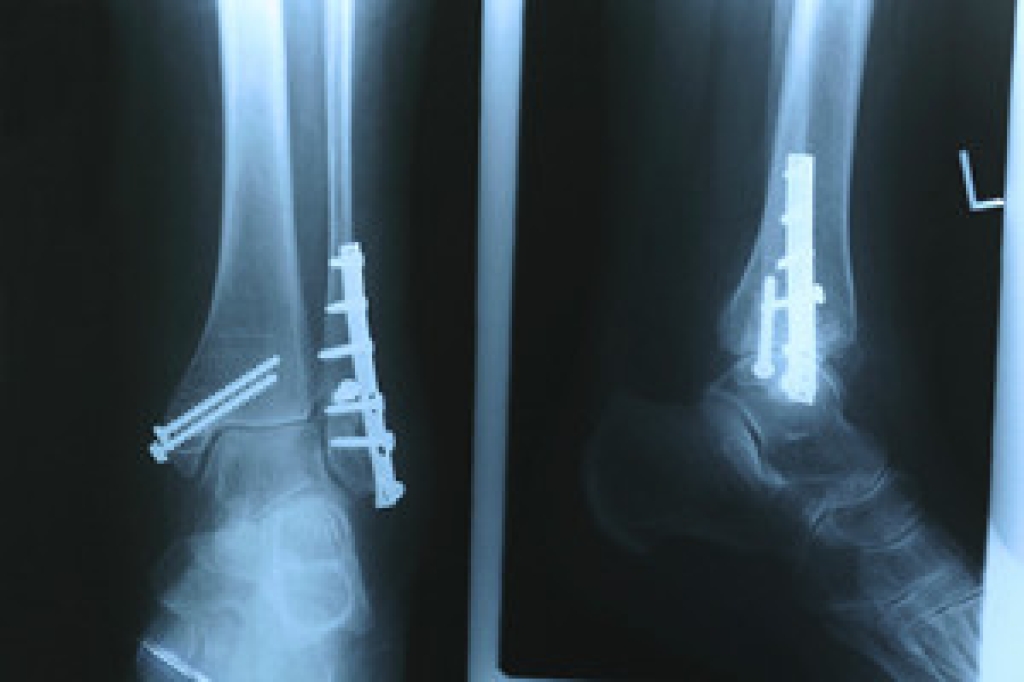

Dealing with Stress Fractures of the Foot and Ankle

Stress fractures occur in the foot and ankle when muscles in these areas weaken from too much or too little use. The feet and ankles then lose support when walking or running from the impact of the ground. Since there is no protection, the bones receive the full impact of each step. Stress on the feet can cause cracks to form in the bones, thus creating stress fractures.

Stress fractures occur frequently in individuals whose daily activities cause great impact on the feet and ankles. Stress factors are most common among:

Pain from the fractures occur in the area of the fractures and can be constant or intermittent. It will often cause sharp or dull pain with swelling and tenderness. Engaging in any kind of activity which involves high impact will aggravate pain.